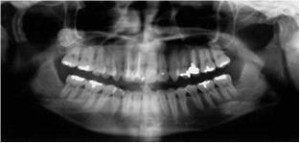

骨の病気ですので、診断にはまずはレントゲンの撮影が必要です。

もっと詳しく診断するにはCT装置による撮影を行い、

歯を支えている骨(歯槽骨)や顎の骨、顎関節の状態まで確認することが必要になります。

なので、診断が大事ですし、診断の時期も重要です。

歯周病の診断は、歯肉溝と言われる歯と歯肉の境目の溝の深さを測るのが一般的ですが、

この検査が実は「歯周病をさらに悪化させている」という現実があるのです。

歯周病の検査、何をするかというと、歯周ポケットの中に

細い針のような検査器具を差し込んで深さがどれほどか測るわけです。